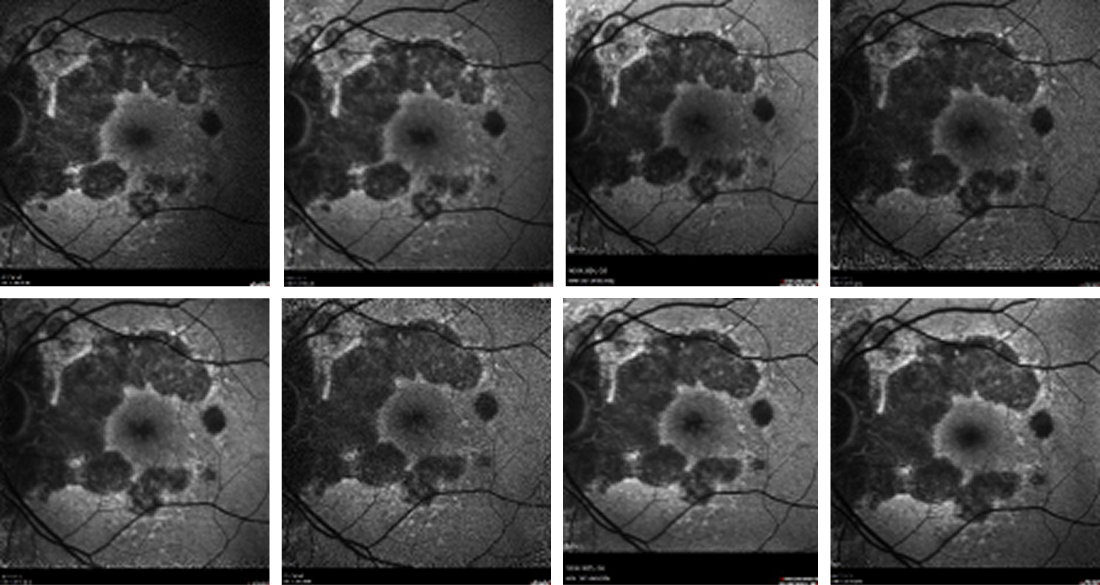

The patient was started on intravitreal pegcetacoplan injections in his left eye beginning in April 2024, and thereafter, monthly for 3 injections. Each visit from Germany included a full clinical examination with slit lamp, biomicroscopy, and OCT and FAF imaging prior to each injection (Figure 2).

<p>Figure 2. FAF imaging of the patient’s left eye taken at each injection visit. Although there was coalescence of the lesions from the time of the first visit (upper left) to the time of the latest visit (lower right), overall, the atrophic area spared the fovea.</p>

Figure 2. FAF imaging of the patient’s left eye taken at each injection visit. Although there was coalescence of the lesions from the time of the first visit (upper left) to the time of the latest visit (lower right), overall, the atrophic area spared the fovea.